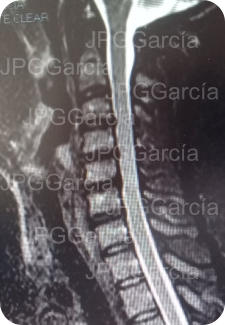

EXTRUSIÓN DE DISCO CERVICAL C4-C5

HERNIACIONES CERVICALES C4 A C6